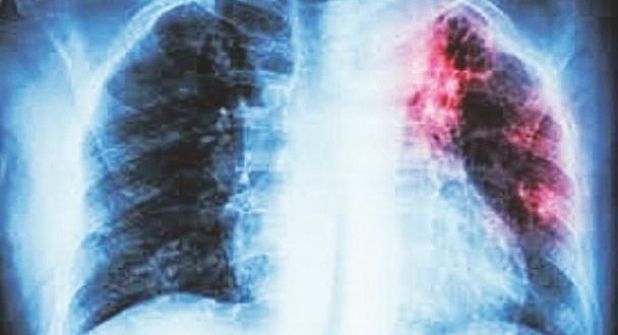

“Buscamos constantemente concientizar a la población y sus familiares del uso del cubrebocas, pero también aquellas personas con más de tres semanas con tos persistente que no se cura con tratamiento tradicional para que acudan a la Jurisdicción y se les haga el seriado de tres muestras, los cuales los resultados están entre 24 y 48 horas, ya que se cuenta con un laboratorio exclusivo y especializado para estos diagnósticos, además de otros tipo de estudios como los rayos equis”, dijo la experta en tuberculosis.